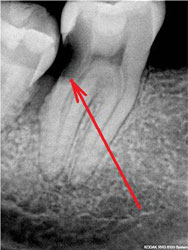

Что касается корневых каналов, то именно здесь и были основные сложности. Оба канала были не слишком здорово обработаны и запломбированы, в результате чего на обоих корнях появились гранулемы.

Но обычный рентгеновский снимок дает плоское 2хмерное изображение, разные структуры накладываются друг на друга, и сложную анатомию каналов на нем не всегда можно разглядеть. Что и произошло в этом случае. Один из каналов имел двойной изгиб. При предыдущем лечении доктор не смог по каким-то причинам этот изгиб увидеть и пройти, уперся в стенки корня, создав т.н. «ступеньку».

Это довольно неприятное осложнение, т.к. при повторном лечении «нащупать» снова реальный ход естественного канала очень непросто. А без этого невозможно рассчитывать на успех лечения. Представьте себе, что Вам надо наощупь, с закрытыми глазами вдеть нитку в самое маленькое игольное ушко… При этом ушко иголки находится в глубине канала диаметром всего 1-2 мм. Примерно с этим каждый раз сталкивается эндодонтист в таких случаях. В решении таких задач нужно большое мастерство, хорошее оснащение, пространственное мышление, изрядное терпение (причем и со стороны пациента тоже), ну, и доля удачи.